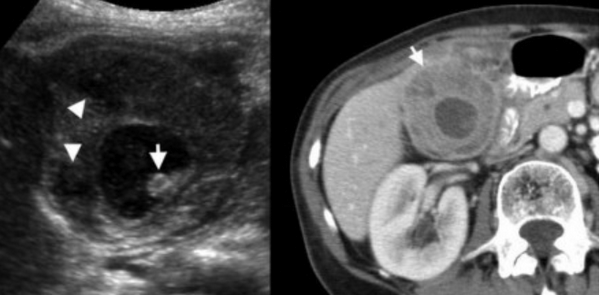

Ксантогранулематозный холецистит — это воспалительное заболевание, характеризующаяся тем, что в стенке желчного пузыря образуются ксантомы и гранулемы. При исследовании выявляют утолщение стенки желчного пузыря, уменьшение органа в размере, а также интрамуральные узелки, которые визуализируются, как гипоэхогенные включения на УЗИ и гиподенсные на компьютерной томограмме. Данные включения схожи с включениями при карциноме желчного пузыря.

УЗИ и КТ желчного пузыря. Ксантогранулематозный холецистит. Слева на УЗИ визуализируется (помечено стрелками) утолщение стенки желчного пузыря с интрамуральным включением и с камнем в просвете органа. Справа на КТ выявляется утолщение стенки с гиподенсными включениями.

Выше представлено КТ пациента 71 года с ксантогранулематозным холециститом. Постконтрастное КТ. Визуализируется утолщение стенки желчного пузыря с включениями, которые соответствуют абсцессу или фокусам воспаления.

УЗИ (слева) и КТ (справа) желчного пузыря. На УЗИ ярко выраженное утолщение стенки желчного пузыря (указаны белыми стрелками). Множественные камни в просвете желчного пузыря (указано стрелкой). Компьютерная томография с контрастным усилением. На КТ визуализируются утолщение стенки с внутристеночными гиподенсными включениями. На КТ также выявлено, что процесс распространился на печень (указано стрелкой).